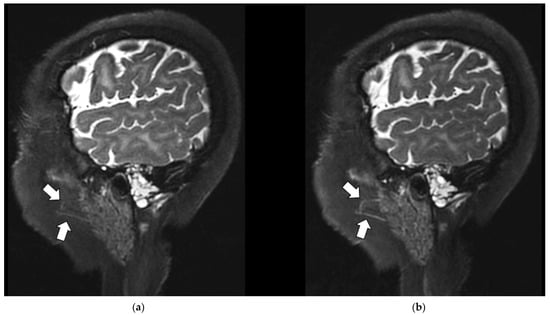

3.3.2. Artifact Enhancement